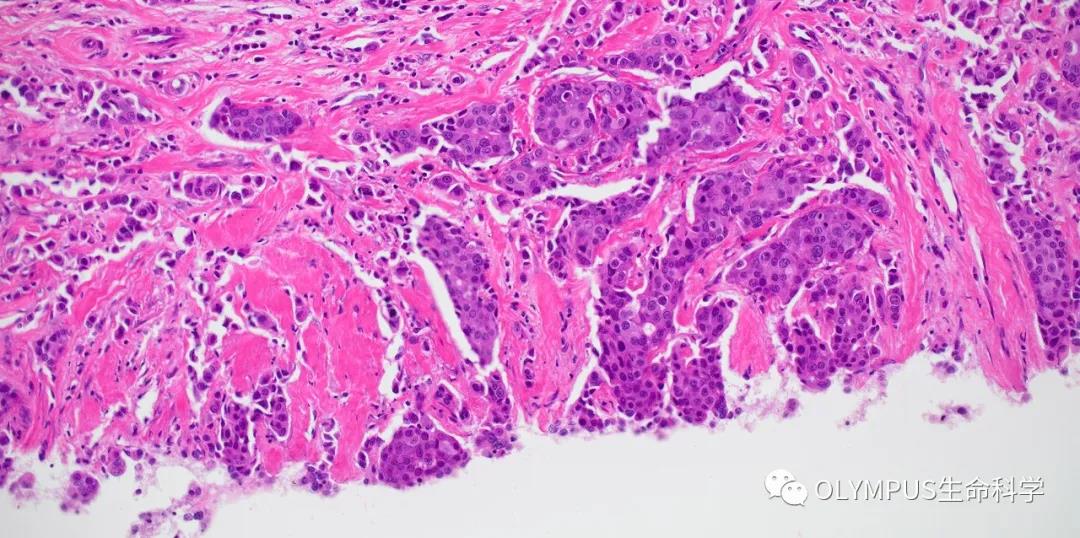

具备4K超高清图像质量的DP28相机让用户能够共享和讨论样品图像的细微之处,而具备640万像素分辨率和每秒45帧速率的DP23相机则能够轻松快速捕捉满足大多数生命科学成像应用细节所要求的图像。

在显示器或大屏幕上显示显微图像时,尽可能高的分辨率以及更快的帧率非常重要。DP28相机的890万像素CMOS图像传感器、全局快门以及4K分辨率(每秒32帧)能够提供出色图像质量。为了捕捉到快速移动样品的流畅图像,相机能够以64 fps采集与标准显示器最大帧率匹配的全高清实时图像。

与DP系列的所有相机一样,这两款相机均能够准确还原色彩,让染色标本看起来与预期别无二致。